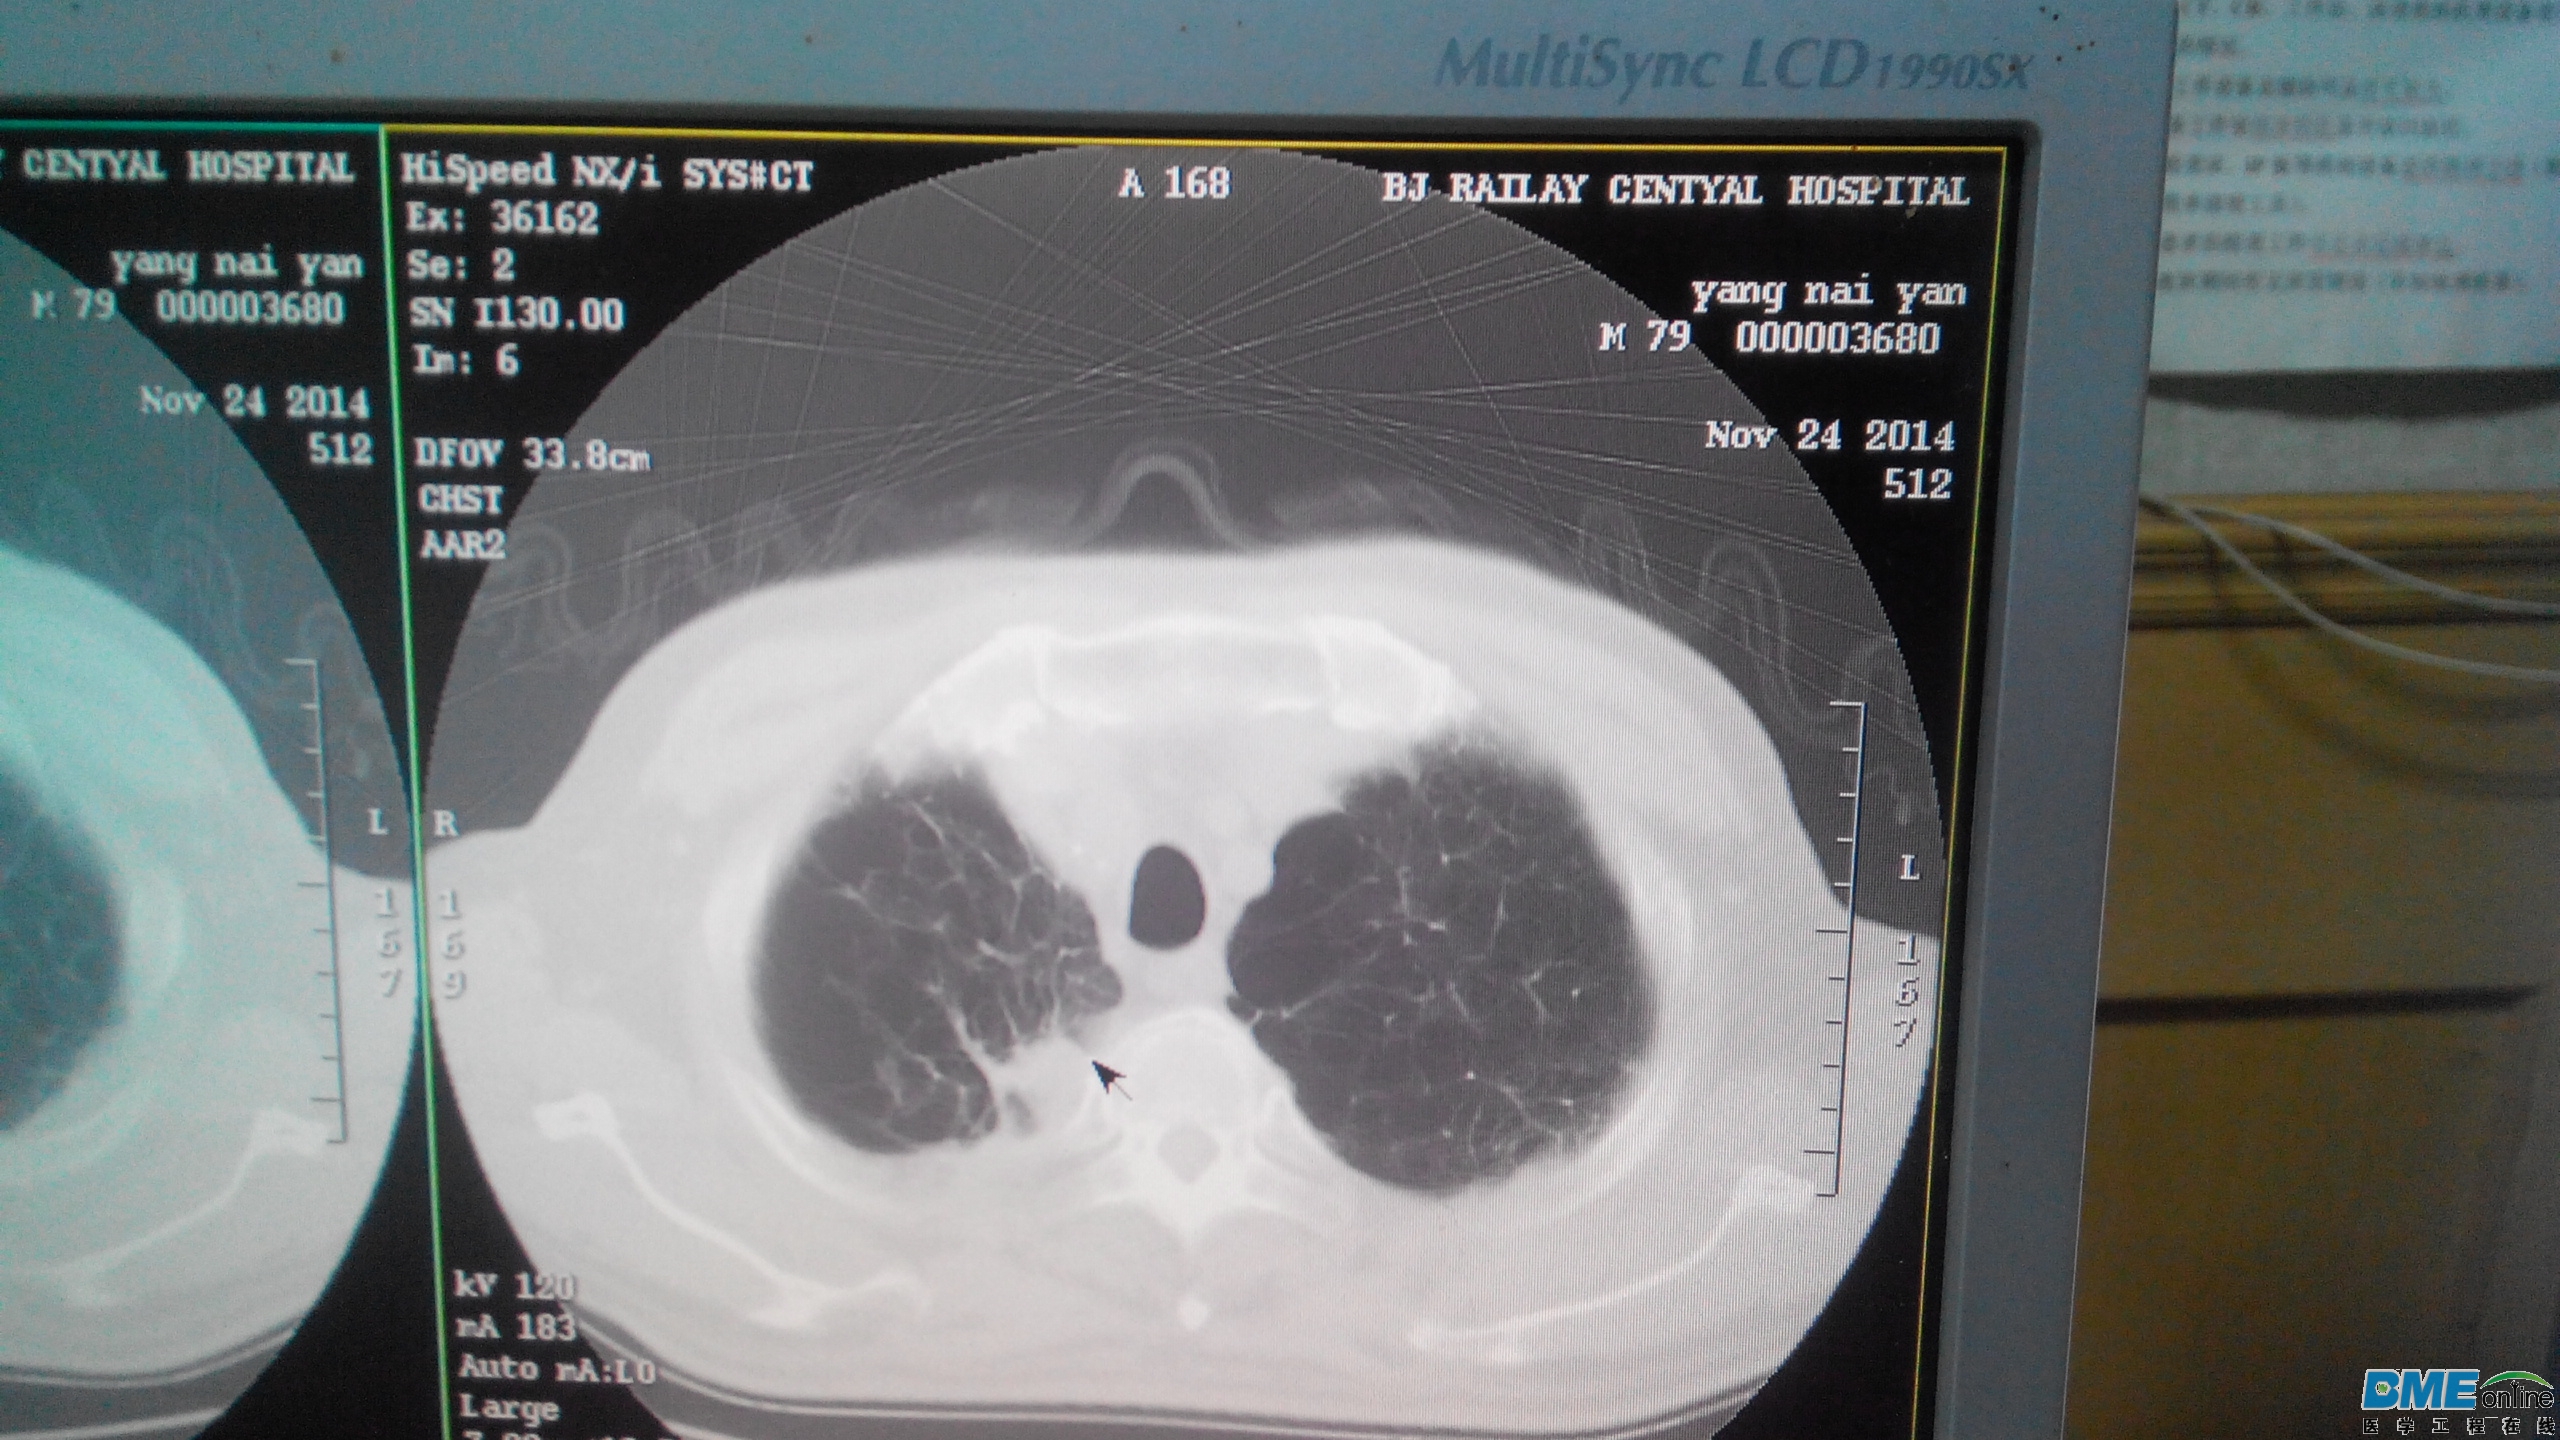

第一个:

此图伪影为无规则线状伪影,开始怀疑是异物,检查未发现异常,机器型号NX/I

切线伪影,可能是通道板故障吧。

球馆有没有打火的故障现象,扫描野开小看看伪影有变化吗

有可能是扫描床上有血迹或造影·剂干扰造成的。

改电压,电流,还有换个扫描部位试试伪影有什么改变

通道问题吧